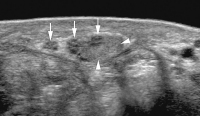

Abbildung 8: Sonographischer Querschnitt durch den Nervus medianus bei einem Patienten nach operativer Versorgung einer Schnittverletzung. Während Teile des Nervs im Nahtbereich eine regelrechte Faszikelstruktur aufweisen (Pfeile), findet sich eine partielle Diskontinuität mit einem exzentrischen Anastomosenneurom (Pfeilspitzen).

Abbildung 9a-b: (a) Sonographischer Längsschnitt durch eine exzentrisch dem Nervus medianus (Pfeile) anliegende Raumforderung (Pfeilspitzen) mit etwas inhomogener feingranulärer Binnentextur. Zusammen mit einer hohen Binnenvaskularisierung im Farbdoppler-Sonogramm (b) typisch für ein Schwannom.